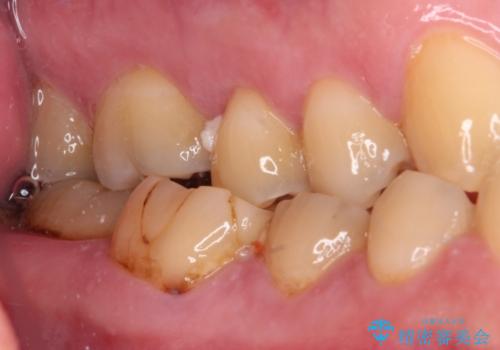

最近ものが挟まりやすくなったり、冷たいものがしみるようになったりと言った症状があり、診査したところ、歯質の欠損や不適修復物などが認められました。

精度の高いセラミックインレーによる修復治療が第一選択となりますが、一方の歯は元々修復物が大きく、咬合力の強い方であったので、セラミッククラウンによる補綴治療を行うこととしました。

長期海外赴任が近いとのことで、出発に間に合うようにアポイントを調整して治療を進めて行きました。

中途半端に歯冠の見えている親知らずもあったため、そちらも出発前に抜歯を行いました。